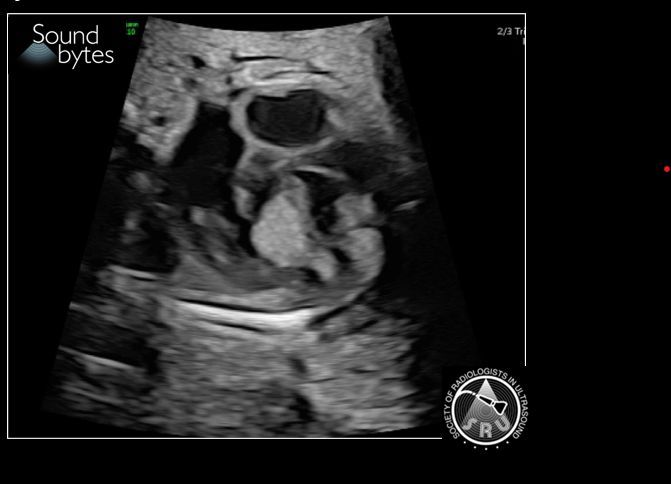

Pregnant woman w history of seizures presents for 2ndT anatomy scan. What's your sound diagnosis? Case courtesy of Dr. April Griffith, U of UT #RadResidents #ultrasound #RadInTraining

Answer: Size Date Mismatch Findings: Discrepancy of >7d in GA by LMP vs US late1st T (9 0/7 wk to 13 6/7 wk) suggests size-dates discrepancy, per ACOG guidelines (below). Case courtesy of Dr. April Griffith, U of UT #RadResidents #ultrasound #RadInTraining